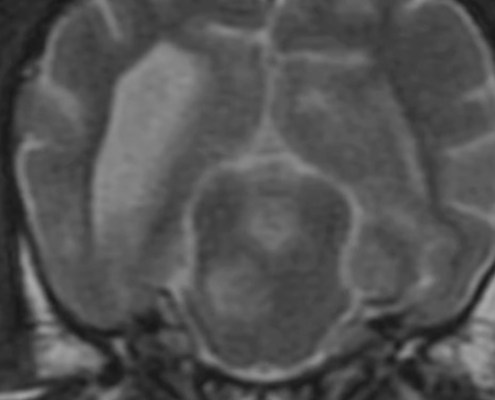

Localize: Circling & ataxic Golden

2yr MC Golden with acute onset of circling, leaning to the left, and lethargy